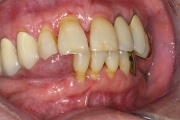

Kõige tavalisem kaebus sülje hüpofunktsiooni korral on püsiv, terve päev kestev suukuivus. Selline seisund nõuab sagedat joomist. Inimesed ärkavad tihti keset öö ja on sunnitud võtma klaasi vett endaga voodisse. Tuleb eristada aga neid, kes ärkavad põhiliselt hommikul, sest suukuivuse Loe edasi »